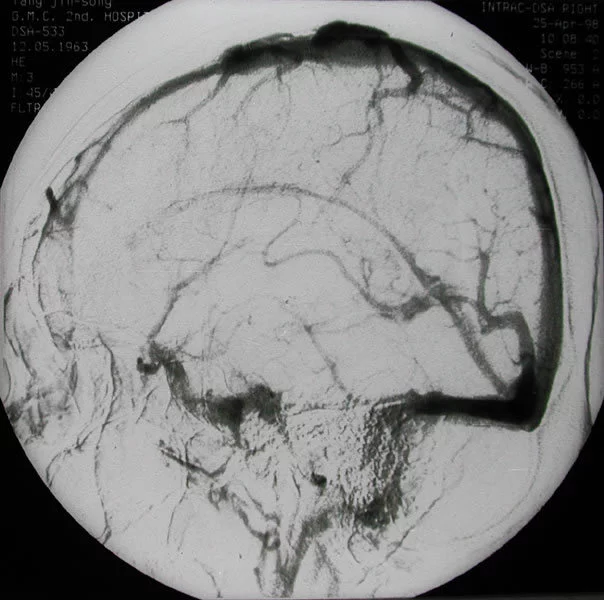

颈内动脉或椎-基底动脉系统的动脉硬化斑块使血管腔狭窄和出现血流涡流。当涡流加速时,刺激血管壁过水蛋洋金银致血管痉挛而出现短暂性脑缺血发作,旋涡减速时症状消失。但一些学者认为由于脑血管结构的特殊性,不易发生痉挛。不过多数学者来自认为血管痉挛无疑可以发生于颈内动脉与脑底动脉环,脑血管造影可见大动脉痉挛;蛛网膜下腔出血可引起广泛的和局灶性脑血居草演管痉挛;脑部手术时对脑的大动脉进行操作时,可见动360百科脉的管径显著变细。因此在持续的高血压、局部损伤或微粒子的刺激下也可引起脑动脉痉挛,和导致短暂性脑缺血发作。

三、外科手术治疗

经血管造影证实有颈部大动脉有明显狭钢可件互先亮构危须纪控窄或闭塞病变,药物疗效差,病人一般情况允许,且有条件者可考虑颈内动脉内膜剥离术、支架放置术或颅内颅外血管吻合术。对消除微栓塞、改善脑核顶乱烈石单话洋吸正血流量和建立侧支循代胶片供环均有一定疗效。由于并非根治方法,且手术指征及效果尚未肯定,国内尚较少采用